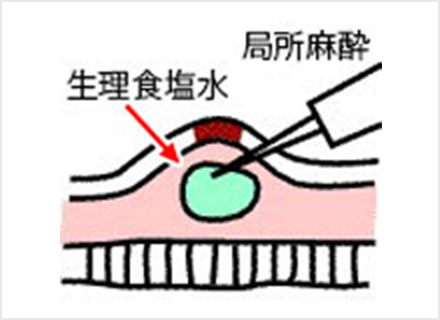

内視鏡的粘膜切除術:EMR(Endoscopic mucosal resection)

スネアと呼ばれる金属の輪を病変部に引っ掛け、高周波電流を流して病変を切り取ります。EMRは、治療が比較的短時間ですみますが、一度に切り取ることができる病変の大きさは、スネアの大きさ(約2cm)までと制限があります。

粘膜下層に薬剤を注入して浮かせた状態にする